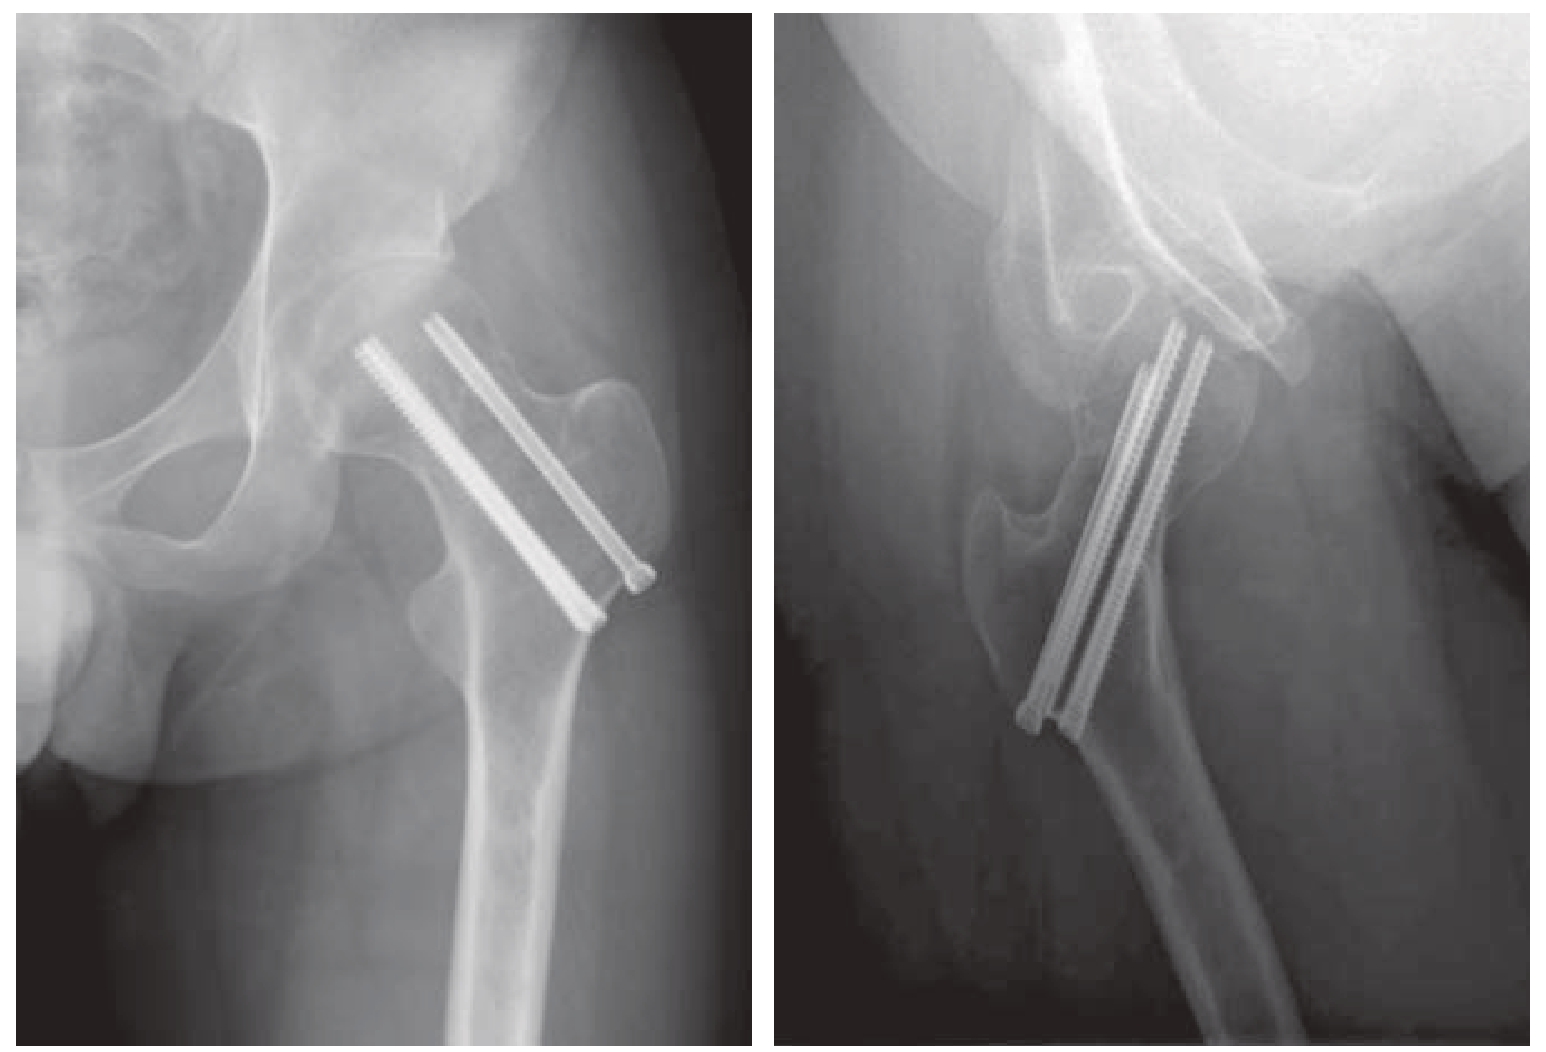

1)α构型螺钉固定:除了平行的PLCS螺钉外,从股骨大转子外侧壁与垂直骨折线正交植入一枚水平或横行螺钉(图9—4),由此而构成的构型被称为α构型螺钉固定。不同文献中对这枚横行植入的螺钉命名不同,总结下来有偏轴(off-axis screw)、横行(transverse screw)、交叉(cross screw)、转子(trochanteric screw)、Pauwels(Pauwels screw)等多种称谓[12,13]。一般建议首先垂直于骨折线植入横行偏轴螺钉可以对骨折线进行加压,其后在沿股骨颈轴线植入平行螺钉。骨折面之间的加压,可以增加抗剪切力[12]。因而,其适应证是垂直型股骨颈骨折。从2012年至今,不断有学者对这种α构型螺钉固定方法进行生物力学评估(表9—1)[14 20]。这些生物力学实验,特别是实体实验用不同的骨标本制作了相同的骨折模型,采用相似的实验方案,得出的实验结论基本趋势一致。α构型螺钉固定方法抗剪切力更强,横行植入的螺钉使整体获得很好的把持力。由于横行植入螺钉的高低,使得横行螺钉出现两种固定形态:单皮质固定和双皮质固定,进而造成不同实验之间的结果也略有差异。

img

图9—4 α构型螺钉固定病例

α构型螺钉固定的临床研究报道并不多。2017年,有学者报道了小样本量的临床系列研究[12]。共20例垂直型股骨颈骨折患者,平均年龄38.7岁,接受了α构型螺钉固定:2枚7.0 mm平行螺钉联合1枚7.0 mm横行螺钉单皮质固定。2枚平行螺钉沿股骨颈轴线偏颈远端植入,横行螺钉则于颈中部植入。经过24个月随访,16例愈合。其中2例骨折不愈合经过转子间外翻截骨刃钢板固定后愈合,2例患者发生股骨头坏死接受全髋关节置换治疗。作者总结认为这种构型的固定方法能够成功治疗垂直型股骨颈骨折。但其20%(4/20)的并发症率还是需要谨慎决策。2019年,中国学者报道了到目前为止病例量最大的一项关于α构型螺钉固定的RCT研究[21],该研究共纳入60例Pauwels Ⅲ型股骨颈骨折病例,平均年龄56.2岁,采用传统倒三角PLCS固定30例,α构型螺钉固定30例。经过平均13个月左右的随访,发现α构型螺钉固定组的髋关节Harris评分(Harris hip score,HHS)高于传统固定组且股骨颈短缩明显减少,而视觉疼痛评分(visual analogue scale,VAS)、欧洲五维健康量表(EuroQol five dimensions questionnaire,EQ—5D)评分及并发症发生率无明显差异。综合目前获得的临床研究结果和生物力学试验结果,α构型螺钉固定的技术细节还需要规范,其治疗垂直型股骨颈骨折的效果还需要进一步明确。